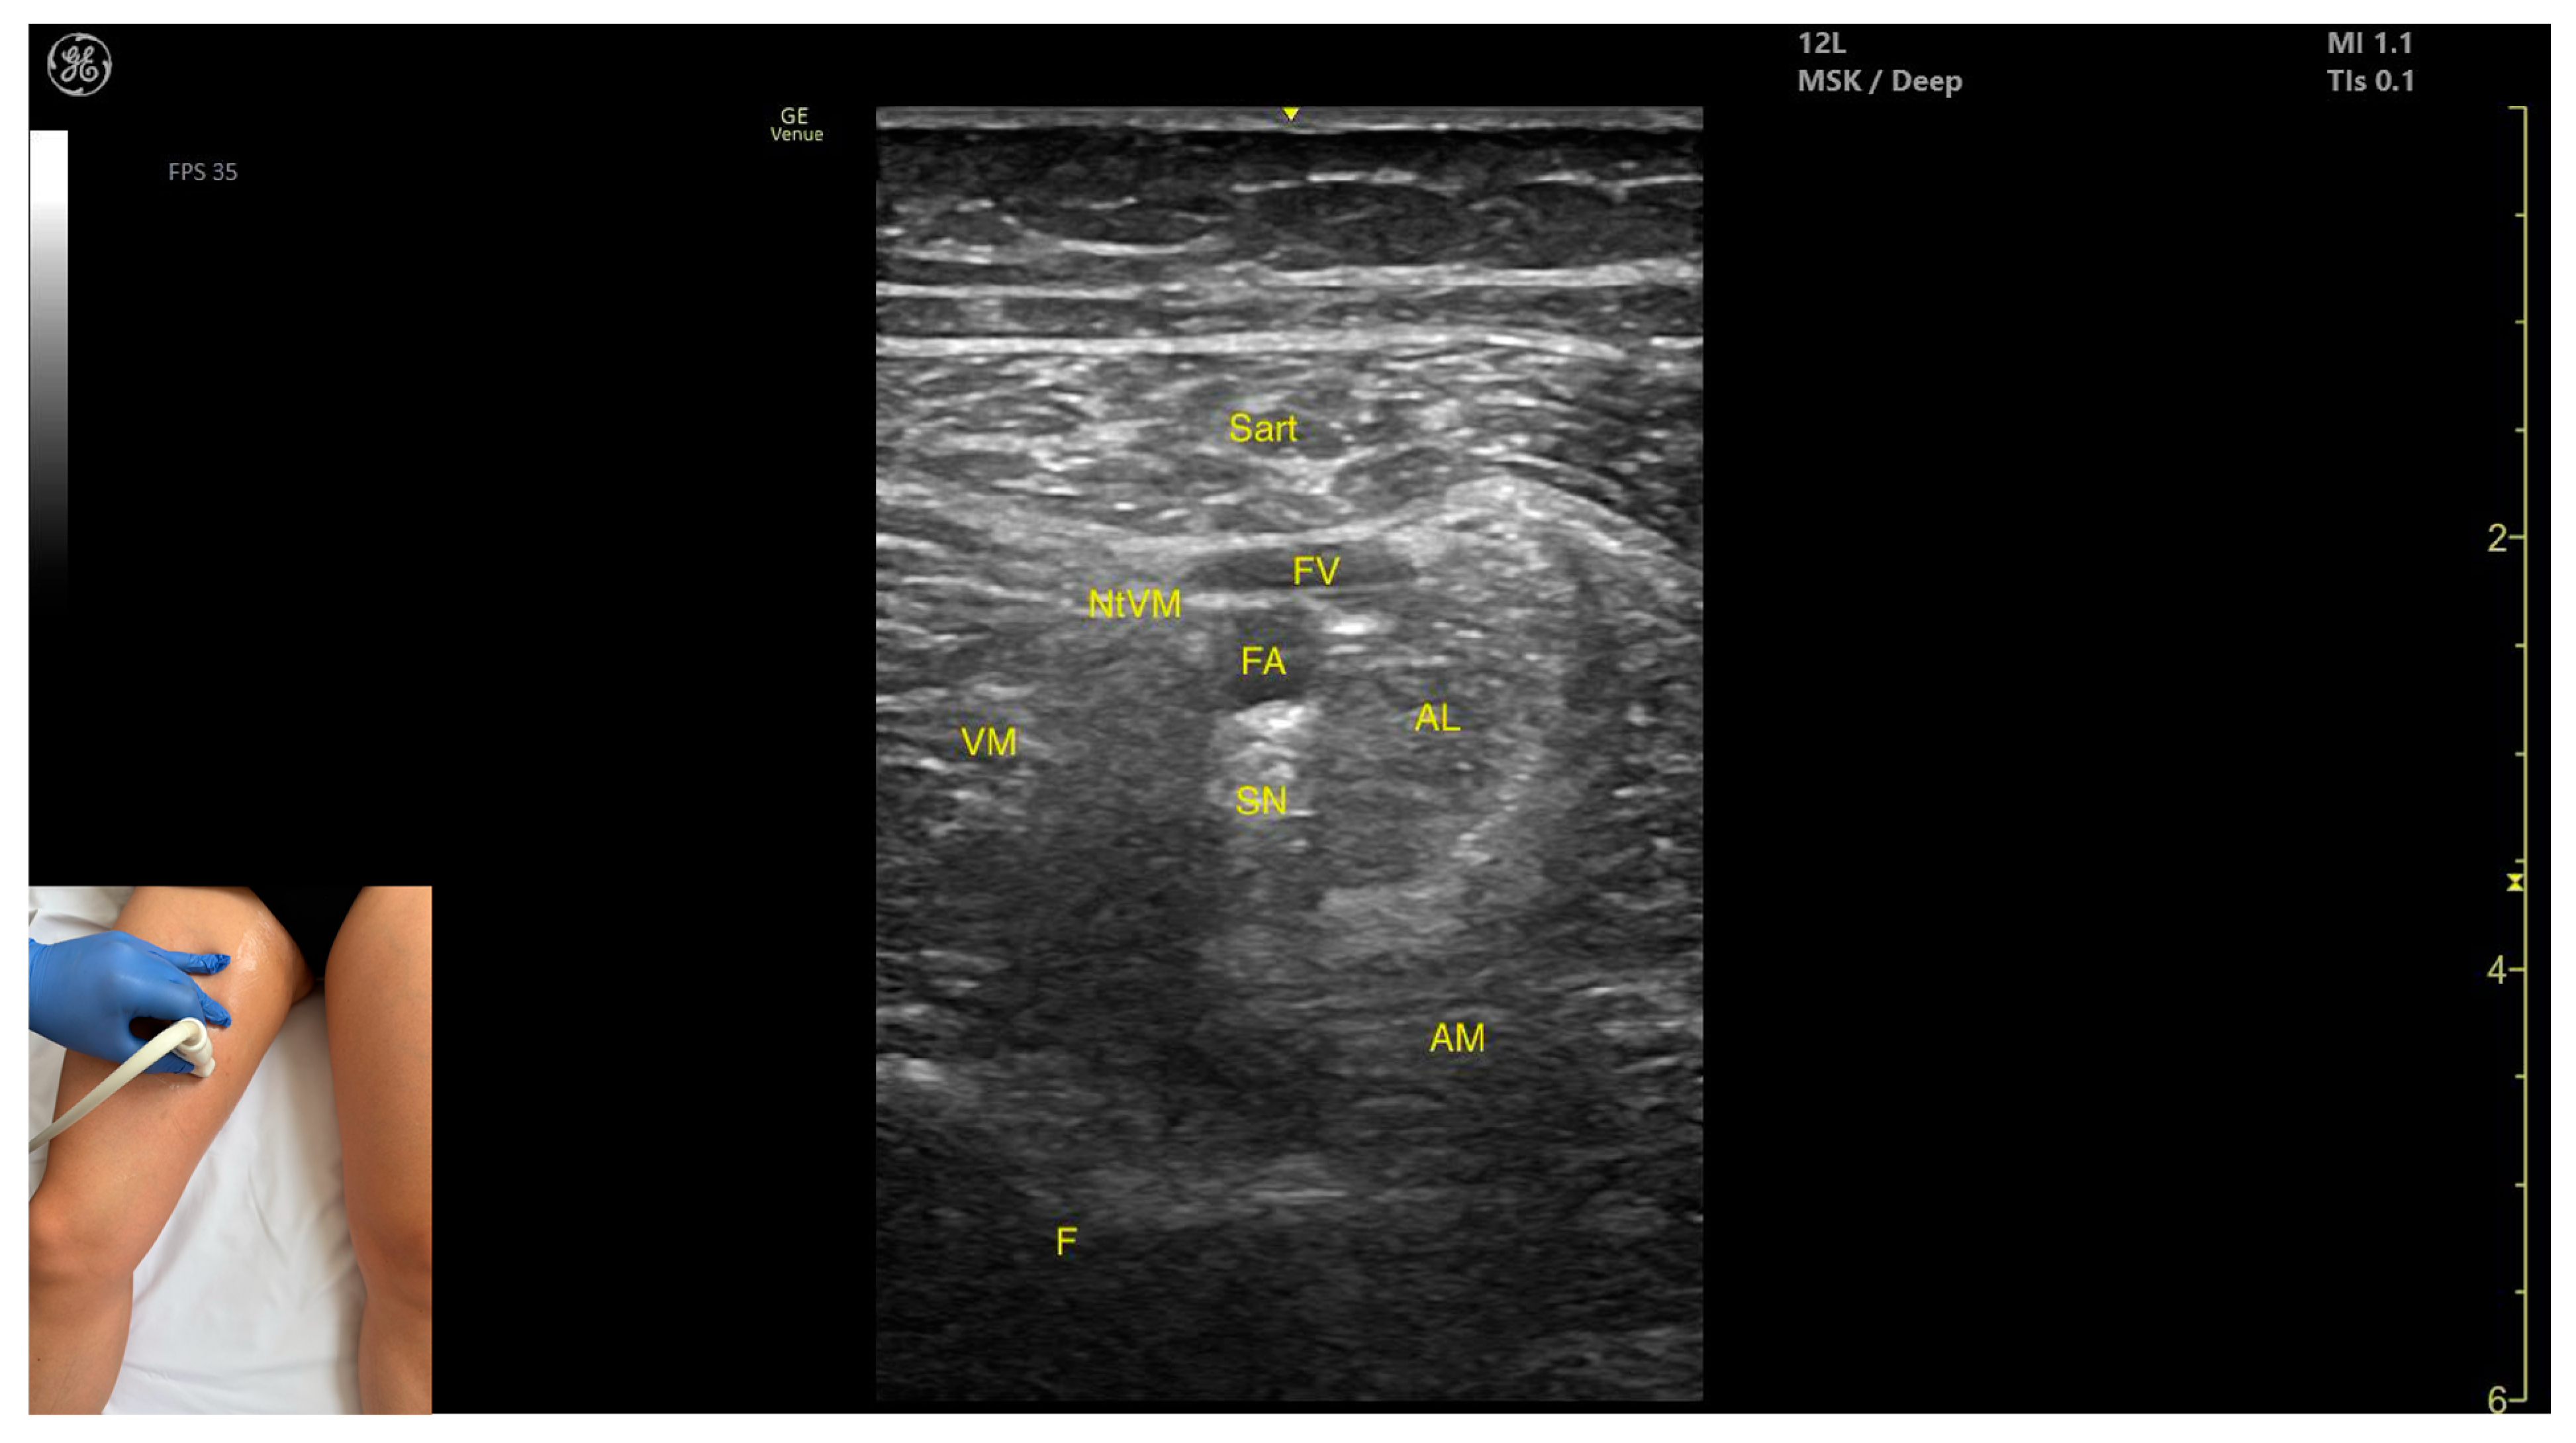

3.5. Sartorius (Sart)

3.5.2. Ultrasound Identification

3.5.3. Key Ultrasound Landmarks

- Muscle position: It is the most superficial muscle in the anterior compartment of the thigh. Deep and lateral to the sartorius lies the vastus medialis; deep and medial to the sartorius lies the adductor longus. At this level, the adductor canal is visualized beneath the Sart, containing the femoral artery, femoral vein, saphenous nerve, and nerve to vastus medialis.

- External fascia: A pronounced fascia separates the Sart from the subcutaneous plane, vastus medialis, adductor longus, and adductor magnus, aiding in precise botulinum toxin injection.

- Dynamic evaluation: During dynamic evaluation, scanning proximally toward the hip joint, at the proximal third of the anterior thigh, the adductor longus thickens medial and deep to the Sart, while the rectus femoris appears deep and lateral. At this level, the adductor canal shifts to lie medial to the Sart and lateral to the adductor longus. During distal scanning toward the knee joint, in the distal third of the anterior thigh, the gracilis is seen medial to the Sart, and the vastus medialis lies deep and lateral to it. Muscle contraction is visible during hip flexion, abduction, and internal rotation, as well as knee flexion maneuvers.

3.5.4. Clinical Implications and Injection Strategy

3.7. Adductor Longus (AL)

3.7.2. Ultrasound Identification

3.7.3. Key Ultrasound Landmarks

- Muscle position: It is the most superficial muscle mass at this level. Lateral to it lies the sartorius muscle, and medially, the gracilis muscle. The adductor canal is also visualized laterally.

- External fascia: It presents a pronounced fascia that separates it from the adductor magnus, adductor brevis, sartorius, and gracilis muscles during botulinum toxin injection.

- Dynamic evaluation: During dynamic evaluation, scanning proximally toward the hip joint, the adductor brevis, which lies deep to the adductor longus, becomes more prominent. Scanning distally toward the distal third of the medial thigh, the adductor longus gradually decreases in thickness until it disappears from view, at which point the gracilis and sartorius muscles become adjacent (Video S2). Contraction is visible during hip adduction and internal rotation maneuvers.

3.7.4. Clinical Implications and Injection Strategy

| Sartorius | Middle third of medial thigh | Adductor canal (deep)—femoral artery, vein, saphenous nerve, and nerve to vastus medialis; vastus medialis (deep and lateral) and adductor longus (deep and medial) | Transverse scan on medial thigh | Avoid structures in adductor canal |

| Adductor Longus | Proximal third of medial thigh | Gracilis (medial), sartorius (lateral), adductor canal (lateral), and adductor brevis (deep) | Transverse scan on upper medial thigh | Confirm muscle position and relations, avoid structures in adductor canal |